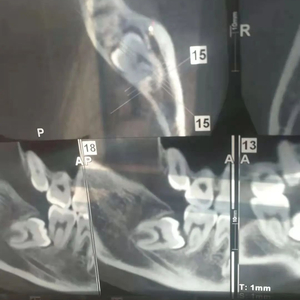

年前的号非常不好约,我再约到某知名口腔医院的号已经是好几天后了。当时我做好了拔牙的准备,前一天晚上大吃了一顿。第二天拔牙时,医生看到X光片觉得情况比较复杂,让我先做牙CT检查明确一下具体情况。

我将片子给医生,下定决心躺到牙医椅上准备“任人宰割”,医生仔细端详了许久,和助手小声讨论了几句,却拿着片子走了。我看到他去和别的医生商量了一会儿,最后摇着头来找我:“你这个智齿埋得太深了,上面的骨头太厚,而且你看,这牙根被吸收了这么多,应该保不住了。我们这边门诊做不了,你得挂个专家号去试试。”

随着医生手指噼啪一通操作,我又被第二家医院“扫地出门”。带着片子走在北京隆冬的街上,我感觉自己因为这两颗牙,变成了什么“疑难杂症”患者,唉……拔个智齿好难! 触目惊心的牙CT结果丨作者供图